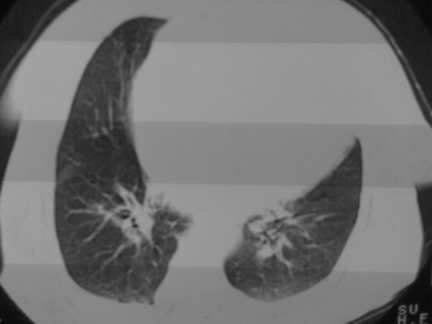

标题: CT13142:女 80 胸闷、气短、1w [打印本页]

标题: CT13142:女 80 胸闷、气短、1w

右肺炎性变,双侧甲状腺肿,胸膜肥厚。

右肺炎性变

双侧胸腔积液

缩窄性心包炎

左室为主的心脏增大。

胸膜肥厚,

气管,支气管软骨钙化。

右肺感染;双侧胸腔少量积液,心影增大,可能与心功不全有关;胸内甲状腺肿。

右肺炎性变,双侧甲状腺肿,胸膜肥厚,心影增大考虑心功能不全.

胸内甲状腺肿;右肺感染;双侧胸腔少量积液。

胸内甲状腺肿;右肺中叶感染;双侧胸腔少量积液;心影增大,考虑有心功能不全。